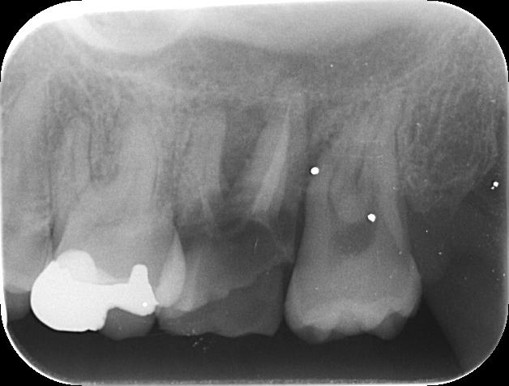

治療前

カウンセリング・診断結果 |

現在の歯の状態は保存が非常に難しく、これ以上無理に残すと周囲の健康な骨や隣の歯にまで悪影響を及ぼすリスクが高い状況です。 |